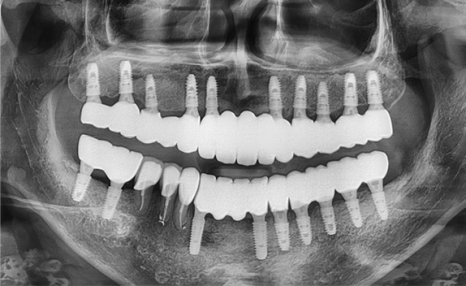

상악동 뼈이식 전 모습 > 상악동 뼈이식 후 모습

상악동 뼈이식 전 엑스레이 > 상악동 뼈이식 후 엑스레이

상악동 뼈이식 수술은 일반 뼈이식 수술에 비해

상대적으로 더 수월한 편이며

수술 후 불편감도 상대적으로 적습니다.

의료진의 적절한 테크닉을 통해

상악동 뼈이식 수술이 잘 이루어진다면

장기적으로 매우 안정적인 결과를 보이고

일상생활 복귀도 빠른 편입니다.